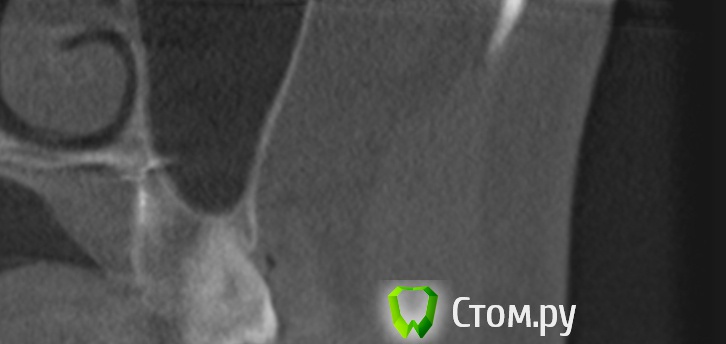

Здравствуйте уважаемые форумчане, подскажите пожалуйста как можно удалить пломбировочный материал за верхушкой небного корня 27 зуба.

Первый раз зуб лечился по поводу пульпита около 14 месяцев назад, второй раз перелечивали каналы в конце зимы этого года. Зуб болит все это время (14месяцев) последние полгода дает кроме тупой периодической боли и неврологические симптомы (покалывания, мурашки, чувство стягивания в щеке и др.), которые больше локализуются в области щеки над этим зубом.

После повторного лечения этого зуба (врач нашел еще один - 4 канал) на 2 недели стало лучше и пропали все неврологические симптомы, но потом опять они усилились с еще большей силой. Месяц назад лежал в стационаре неврологии, после лечения стало еще хуже, такое чувство что все нервные окончания возле этого зуба регенерировали, этот зуб стал болеть почти постоянно, когда его пошатать со стороны в сторону усиливались подергивания в щеке над зубом.

Говорят что источником всего этого есть пломб.материал за верхушкой этого зуба. Какие варианты могут быть по удалению материала за верхушкой?